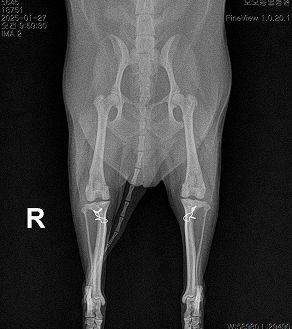

BEFORE

AFTER